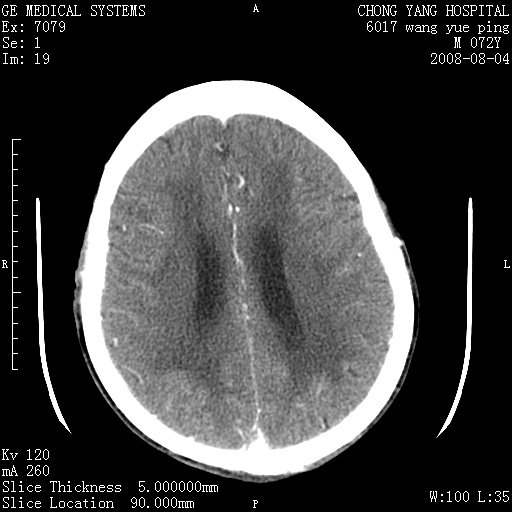

标题: CT14987:M72Y,头痛头昏,BP220/110. [打印本页]

标题: CT14987:M72Y,头痛头昏,BP220/110.

1)考虑左侧小脑脑梗塞。2)脑白质病。3)脑萎缩。4)双侧鼻腔新生物(息肉?)并阻塞性副鼻窦炎。

1.左侧小脑大面积梗塞;2.左侧基底节区腔梗;3.白质疏松;4.脑萎缩;5.慢性副鼻窦炎

小脑左侧病灶呈扇形分布,增强后未见明显瘤体样节结影,病变区未见强化。

支持:左侧小脑脑梗塞梗塞表现

另:脑白质病。脑萎缩。双侧鼻腔新生物(息肉?)并阻塞性副鼻窦炎。

1)考虑左侧小脑脑梗塞,建议治疗后复查除外其他,左基底节区腔隙性脑梗塞2)脑白质变性3)脑萎缩。4)双侧鼻腔新生物(息肉?)并阻塞性副鼻窦炎。